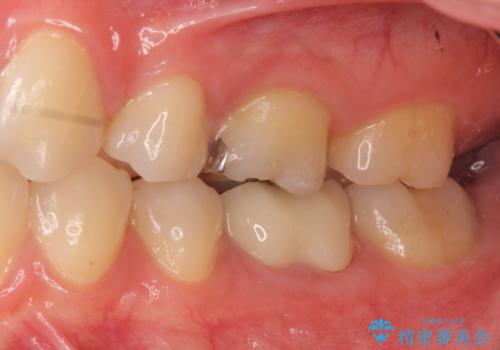

セラミックインレー 下の一番奥歯 歯ぐきの厚みを減らしてぴったりに入れます(ディスタルウェッジ+骨外科)

左下7番には、矯正治療前に虫歯をとり、CRで充填していました。

ただし、元のインレーが遠心マージンが縁下だったため、矯正治療後に歯ぐきの厚みを減らして、しっかり歯ぐきの上にマージンラインが来るように整える手術(ディスタルウェッジ)を行いました。